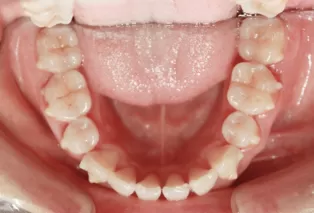

Intraoral photos